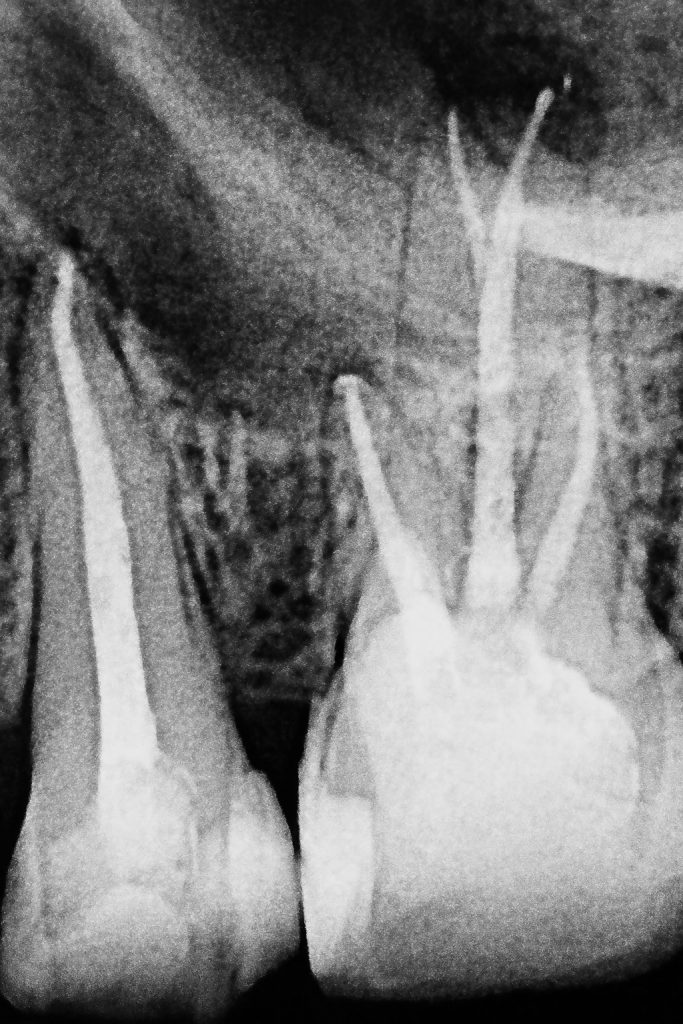

- Rotary NiTi system was used for shaping; irrigants included 5.25 % NaOCl and 17 % EDTA, both sonically activated for effective disinfection. (Fig 3–4)

3. Three-Dimensional Obturation

Obturation was performed using bioceramic sealer with warm vertical compaction, ensuring a dense, continuous fill into the palatal split and accessory canals. Post-operative radiograph confirmed ideal obturation and apical control. (Fig 7)

- Radiographically: Perfect obturation of the palatal split with bioceramic sealer and uniform adaptation.